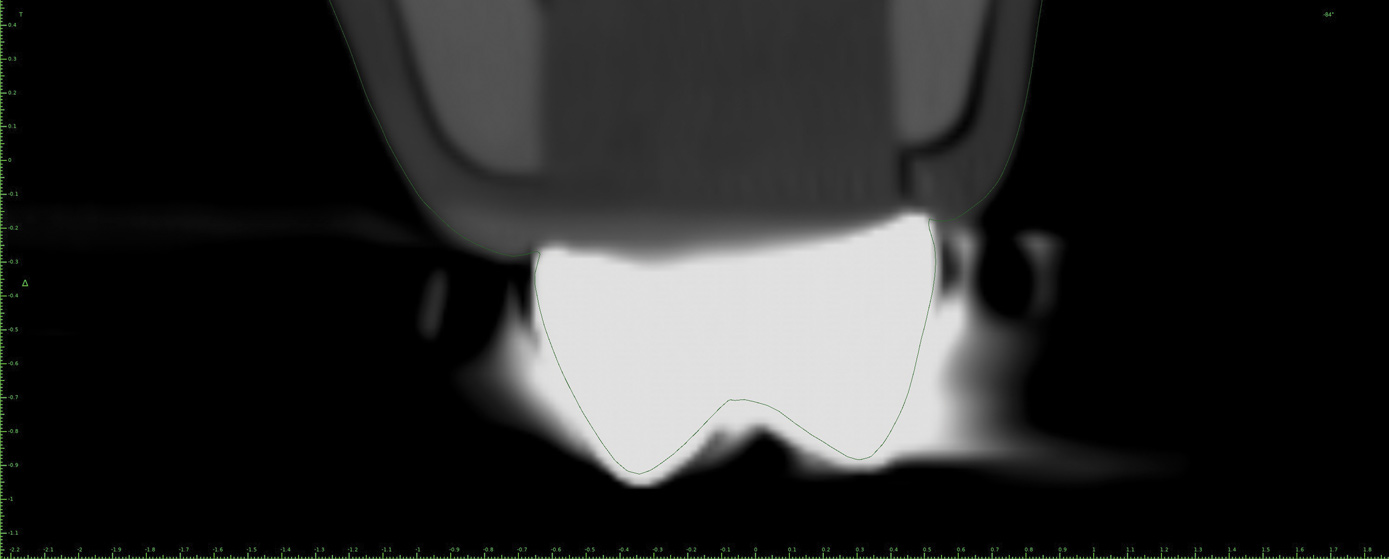

Fig 8. Thin slice at the level of the metal crown in Fig 7 with no MAR used. The outline relates to the stone model of the teeth. Blooming due to metal artifacts can be noted.

Figure 8

Fig 9. Thin slice at the level of the metal crown in Fig 7 with low-level MAR used. The outline relates to the stone model of the teeth. The metal artifacts have been reduced considerably.

Figure 9

Fig 10. Thin slice at the level of the metal crown in Fig 7 with mid-level MAR used. The outline relates to the stone model of the teeth. Some distortion of the shape of the crown on the CBCT can be seen.

Figure 10

Fig 11. Thin slice at the level of the metal crown in Fig 7 with high-level MAR used. The outline relates to the stone model of the teeth. Improvement of the shape of the metal crown can be seen with absence of metal artifacts and a possible improvement in the outcome of the registration procedure.

Figure 11